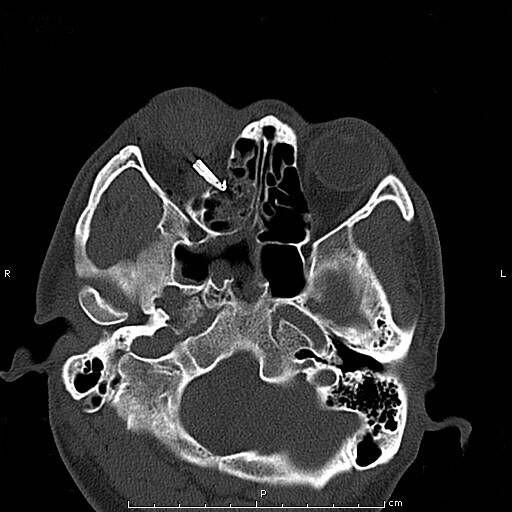

患者青年男性,因“右眼被鋼筆戳傷2小時余”入院,眼科查體:視力:右無光感,左0.4。眼壓:右不能檢查,左正常。右眼上瞼紅腫,鋼筆自顳上方眼瞼刺入,末端位置不詳,睜眼困難;結(jié)膜充血、水腫,角膜尚清,前房積血,余眼內(nèi)結(jié)構(gòu)窺不入。左眼未見明顯異常。入院后完善眼眶CT檢查,印象:右眼眶異物并右眼球破裂傷、眶內(nèi)壁骨折,異物嵌頓于眶壁。鋼筆內(nèi)含墨水,傷情重且復(fù)雜。

經(jīng)科室討論、充分評估患者病情,與患者進(jìn)行病情溝通后,擬于全麻下實(shí)施右眼眶壁異物取出+眼球破裂傷清創(chuàng)縫合探查+眼瞼皮膚裂傷清創(chuàng)縫合+萬古霉素玻璃體腔注藥術(shù)。由于鋼筆筆尖與筆筒游離且筆尖彎曲倒鉤于眶壁,使異物取出難度大大增加,經(jīng)專家團(tuán)隊(duì)討論,決定在鼻內(nèi)窺鏡協(xié)助下聯(lián)合眶內(nèi)入路分離、截?cái)鄡?nèi)直肌、下直肌成功將眶內(nèi)壁異物自鼻腔完整取出,手術(shù)取得圓滿成功。